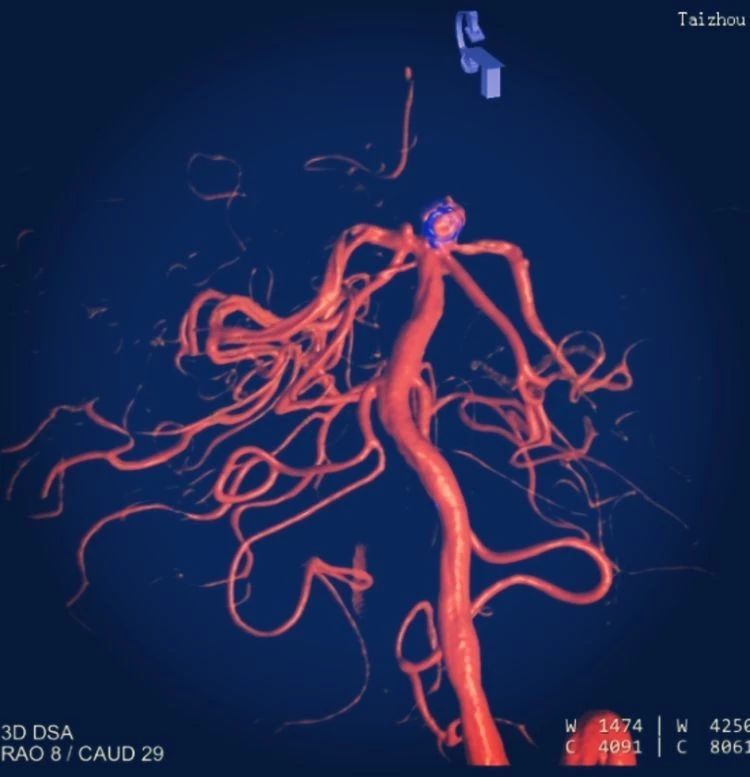

術(shù)中影像重建顯示的不同角度的動脈瘤,看起來很漂亮哦

彈簧圈在顱內(nèi)支架的保護下完美植入

術(shù)后造影顯示,動脈瘤被致密栓塞

術(shù)后的動脈瘤長這樣。因為動脈瘤里填充了彈簧圈,所以在X線照射下整體看起來是黑色的

術(shù)后彈簧圈和顱內(nèi)支架的影像重建。圓球形的是彈簧圈,麻花樣的就是顱內(nèi)支架。